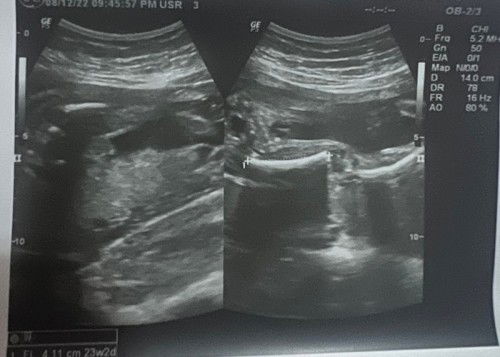

boy po,saken din boy daw pero 70% hindi kc nakita ung itlog ung lawit lng naakita😅😅

Boy 😊 mukhang turtle shape kase same sa baby ko.

saken po kaya ano gender